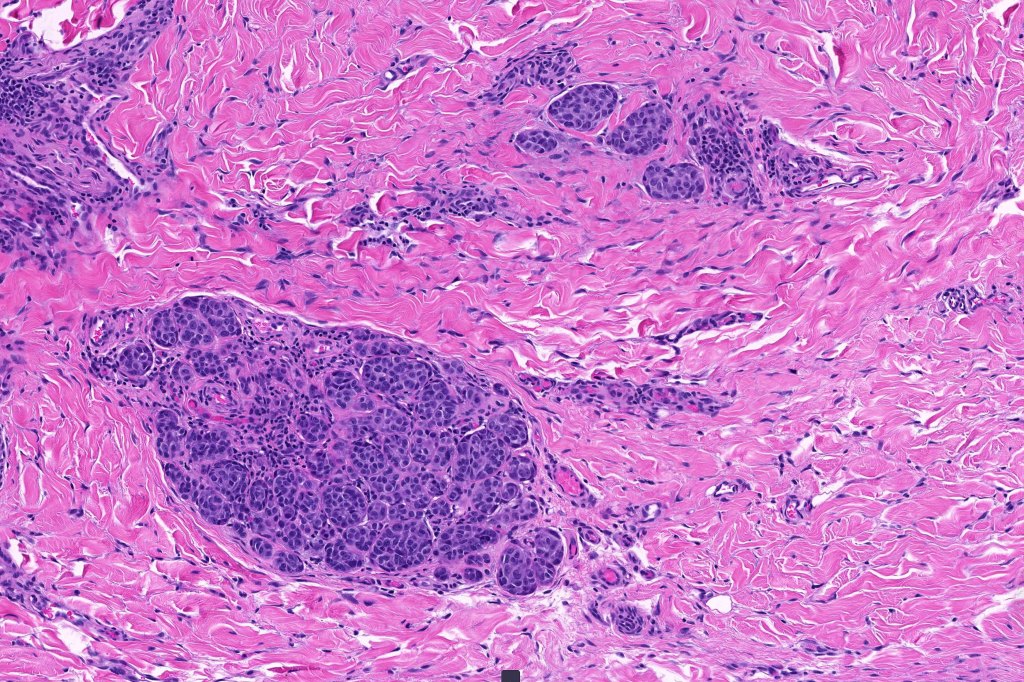

Histological features

•>5-10 mm

•Involve deep dermis or subcutis

•Asymmetrical, poorly circumscribed

•May show effacement/consumption of epidermis or ulceration

•Peripheral Pagetoid spread

•Large nodules which often show impaired maturation

•Loss of gradient with HMB45 and Ki67

•>20% Ki67 expression

•TERT promoter & PTEN mutations

•DNA copy-number variations